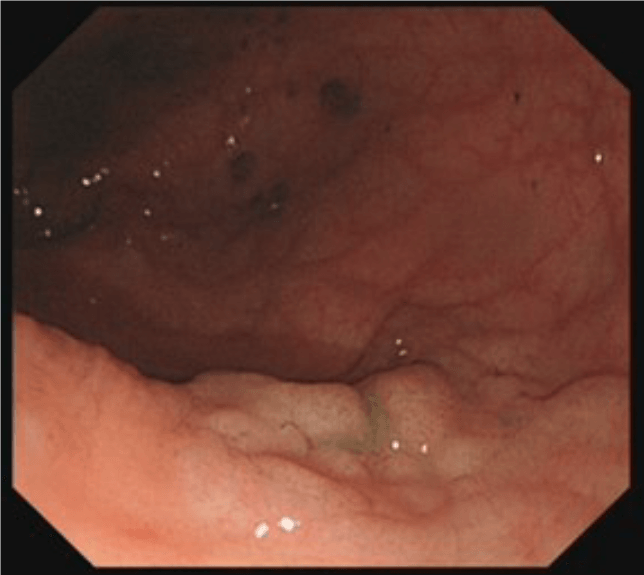

Colonoscopy involves passing a flexible tube (see image alongside) through the anus into the rectum and steering it around the colon. Some images of typical appearances are shown at the bottom of this page (hover over the images for a description).